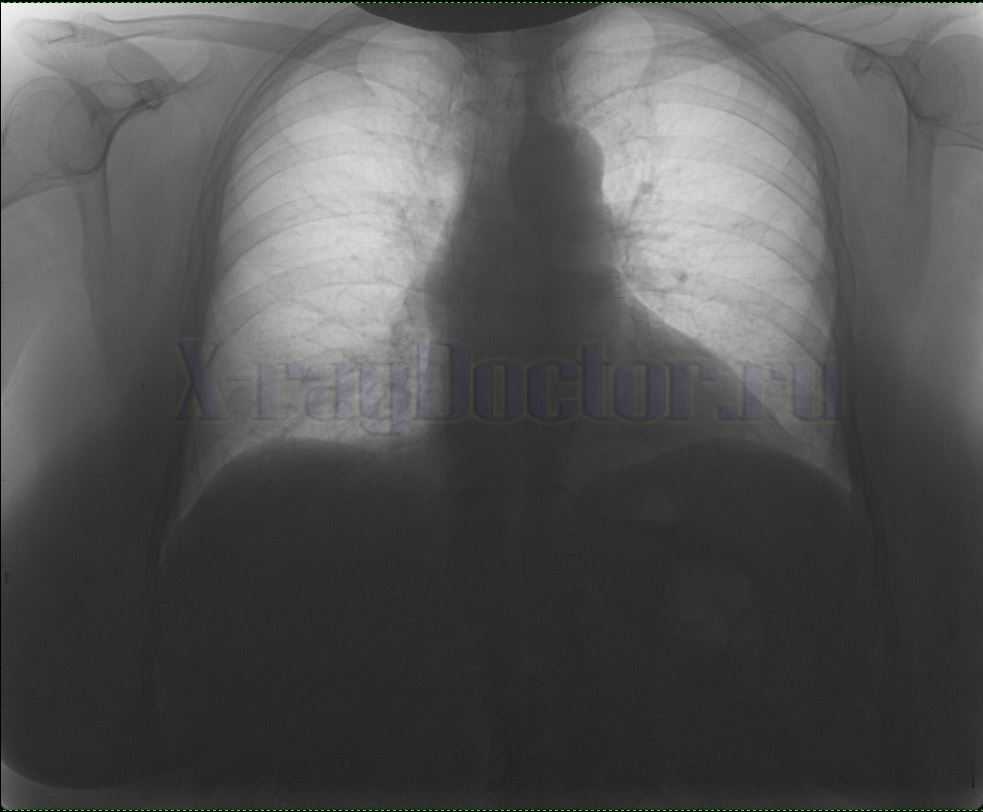

Нормальная цифровая рентгенограмма легких в позитивном отображении

На рисунке приведена нормальная рентгенограмма легких. Запомните ее вид. Если на снимке обнаружите дополнительные пятна, которые отличаются от вышеприведенного фото, скорее всего, такая картина будет отражать патологический процесс.

Снимки легких у здоровых и больных пациентов отображают одни и те же структуры: легочные поля с обеих сторон от позвоночного столба, в центре – тень от сердца, в верхней части снимка видны ключицы, а в нижней части – купол диафрагмы. На легочные поля проецируются тени ребер.

Рентген легких здорового человека описывают по классическому стандарту. В первую очередь вносят данные о состоянии легочных полей, затем описывают корни легких, диафрагмальные купола и реберно-диафрагмальные синусы, потом оценивают состояние сердечной тени и мягких тканей.

Пример описания нормальной рентгенограммы легких:

- В легочных полях отсутствуют видимые очаговые и инфильтративные тени.

- Корни нормальных размеров, структурны, не расширены.

- Контуры диафрагмально-реберных синусов и диафрагмы без патологий.

- Тень сердца обычной формы.

- Мягкие ткани без особенностей.

В норме на снимках купола диафрагмы расположены на уровне шестых ребер, при этом правый купол немного выше. В центре снимка нередко можно увидеть два или три грудных позвонка, остистые отростки которых в норме лежат между ключицами на равном расстоянии от них. Также в центре должна проецироваться тень трахеи, тень сердца в норме должна выступать справа не более чем на 1 см, а с левой стороны она не должна заходить дальше среднеключичной линии.

Корнями легких условно называют бронхиальные разветвления в легочной ткани, в норме они имеют четкую структуру. В них могут быть обнаружены увеличенные лимфатические узлы. Сосудистый рисунок не прослеживается в периферических отделах легких. Реберно-диафрагмальные синусы должны быть свободные.

Рентген здоровых легких должен демонстрировать следующие показатели:

- Легкие занимают правильное положение относительно других структур грудной клетки.

- Количество легочных долей – пять.

- Легкие имеют мешковидную форму, их вершина округлая.

- Размеры легких соответствуют возрастным показателям.

- Легочный рисунок отличается интенсивностью и четкостью.

- Легочные контуры не размыты.

- На легочных полях нет очаговых и инфильтративных теней.

- Корни легких имеют нормальные размеры, они не расширены и обладают четкой структурой.

- Отсутствуют патологии диафрагмы и диафрагмально-реберных синусов.

- Форма сердечной тени обычная.

- У мягких тканей нет патологических изменений и выраженных особенностей.